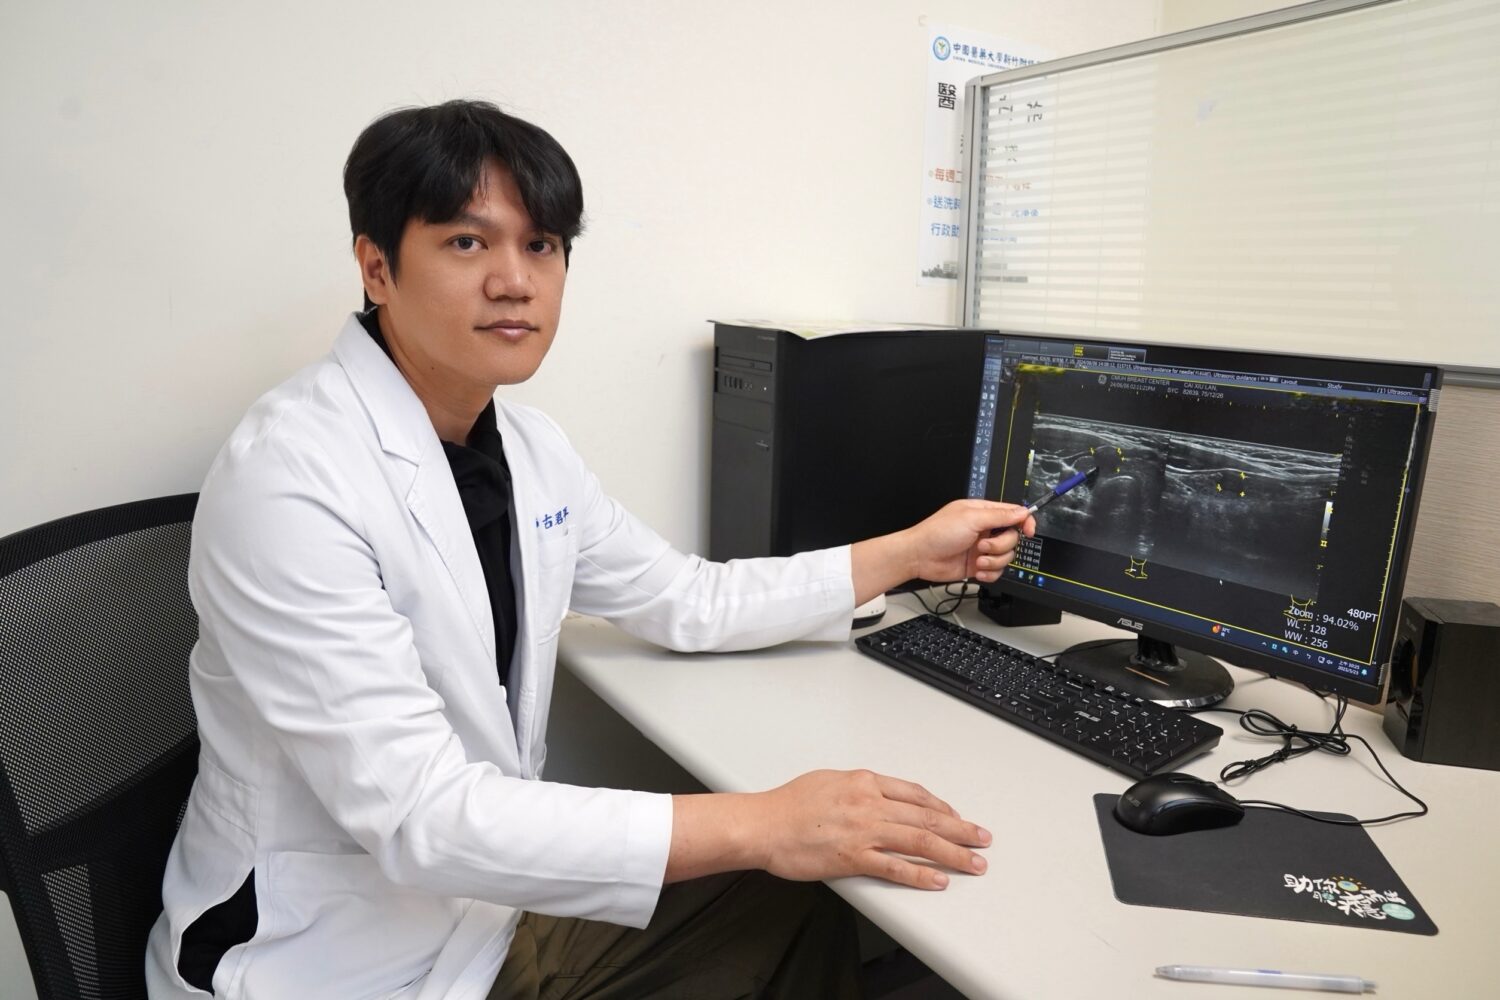

一名48歲女性在健檢中發現甲狀腺結節,經中國醫藥大學新竹附設醫院一般外科古君平醫師持續追蹤兩年,最終確診為第一期乳突狀甲狀腺癌,並合併甲狀腺亢進,經充分討論後,患者選擇接受甲狀腺全切除手術,術後雖出現低血鈣併發症,導致手腳麻木等不適,經靜脈與口服高劑量鈣劑及維他命D治療,目前已穩定恢復。

古君平醫師指出,甲狀腺全切除手術常見兩大併發症為「喉返神經受損」與「副甲狀腺受損」。若副甲狀腺功能受影響,會造成血鈣濃度降低,進而引起手麻、腳麻、肌肉抽搐等低血鈣症狀,該名患者術後血鈣最低降至7點多mg/dL(正常應為8.6 mg/dL以上),經專業治療後逐步改善;古醫師也強調,甲狀腺癌早期發現與積極治療相當關鍵,最常見的乳突狀甲狀腺癌預後良好,約佔所有甲狀腺癌八成以上,多數患者經完整手術切除後搭配定期追蹤,能有效控制病情並長期穩定,甲狀腺全切除後,需終身服用甲狀腺素藥物以維持新陳代謝正常,應依醫囑服藥,不可任意停藥或自行調整劑量,以免影響病情控制或增加復發風險。

此外,古君平醫師也提醒民眾,雖然甲狀腺結節常見,九成以上為良性,但若出現大於1公分或影像異常的情形,應進一步接受細針穿刺檢查,建議每3到6個月定期做甲狀腺超音波檢查,及早偵測惡性變化,掌握治療黃金期。